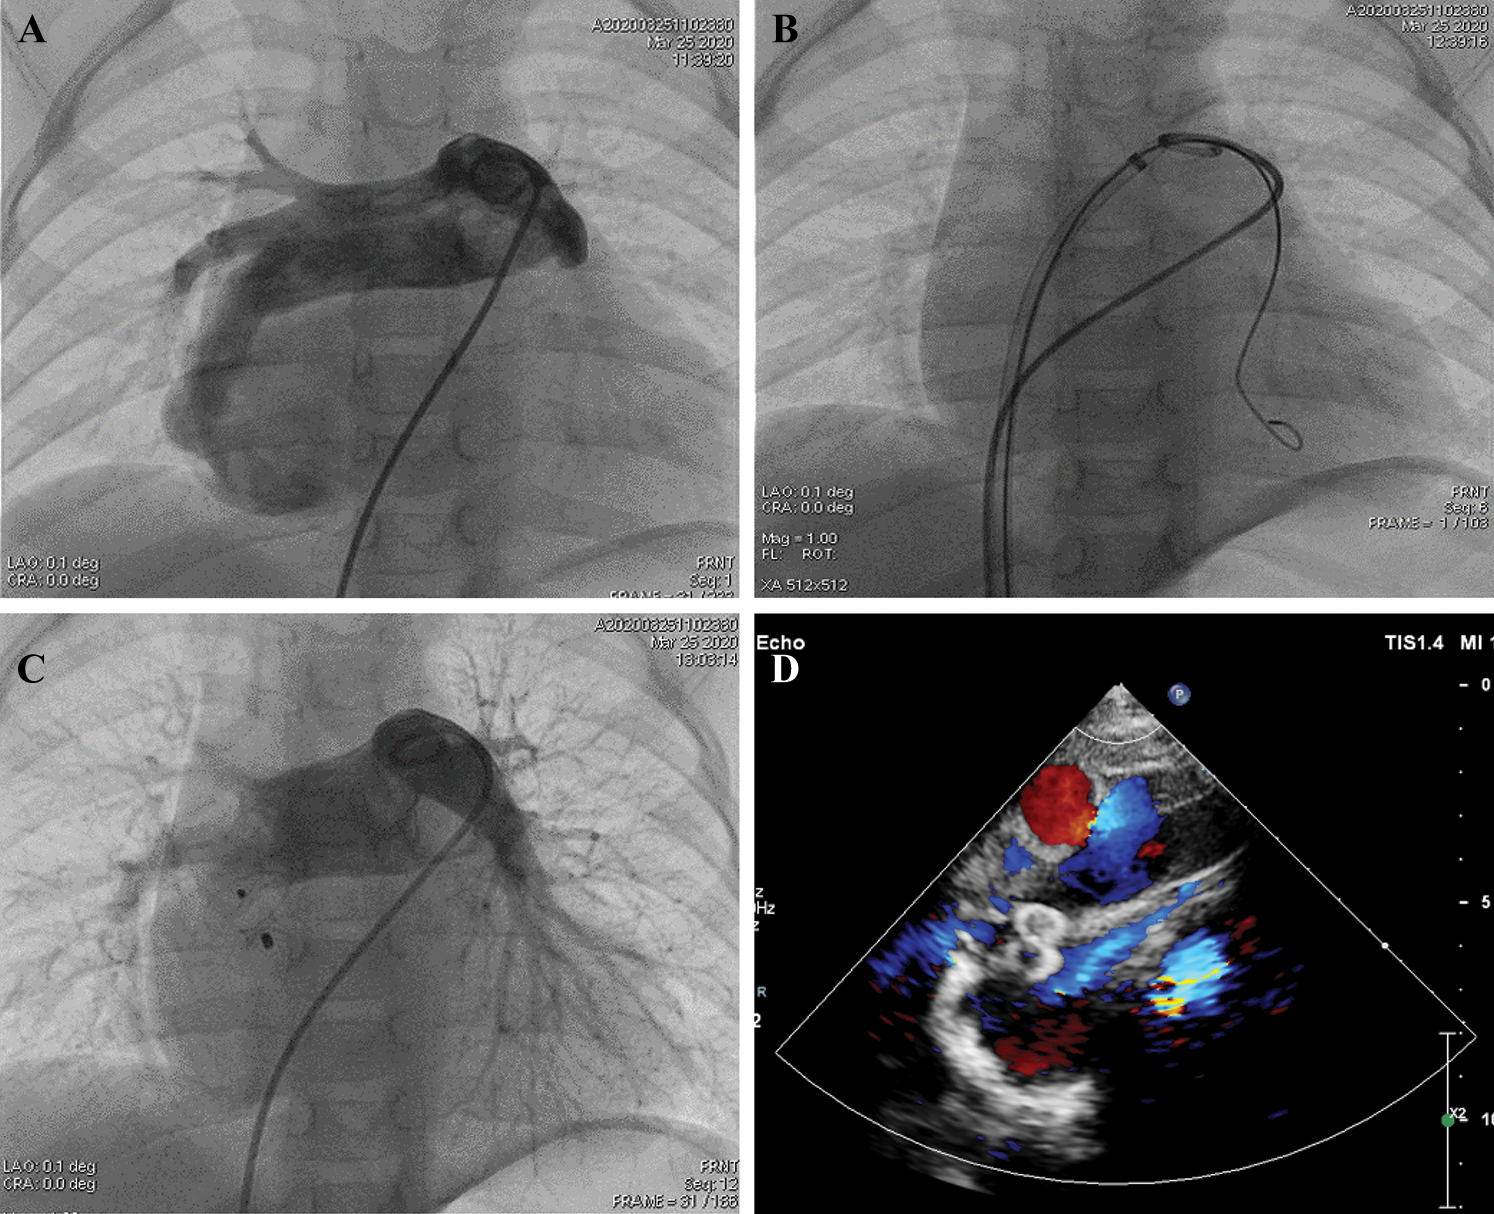

A standard cardiac catheterization was performed, and the right femoral artery and vein were punctured during the operation. The patient’s pulmonary artery pressure was 21/13/17 mmHg. Her blood oxygen level was 86.6% in the descending aorta with a fraction of inspired oxygen (FiO2) value of 40%. Pulmonary arterial trunk angiography showed a fistulous communication between the RPA and LA. The shunt was approximately 7.4 mm × 7.6 mm (diameter × length) (Fig. 2A). The RPA was expanded secondary to the shunt, and the left pulmonary artery appeared comparatively narrow. After the left femoral vein was punctured, we chose an 8F long sheath and established the path from the right femoral vein to the inferior vena cava and to the right atrium through the atrial septal defect. The path continued to the LA fistula and ended in the right inferior pulmonary artery (Fig. 2B). After that, a VSDO-I08 Occluder (Shanghai Push Medical Device Technology Co., Ltd.) was inserted to the narrowest area of the fistula. Her percutaneous oxygen saturation immediately increased from 89% to 99%. Then, the 5F pigtail catheter was inserted from the left femoral vein to the pulmonary artery to confirm the pulmonary venous return was not influenced by the occluder. A second pulmonary arterial trunk angiograph showed no residual shunting of the fistula or change in pulmonary venous return. There was no atrial-level shunting after transcatheter device closure was completed. We released the occluder, and echocardiography confirmed proper placement with no residential shunting (Fig. 2C). Further, there was no shunting observed at the atrial septal defect. Her blood oxygen saturation increased to 99.9% in the descending aorta postoperatively. The next day, echocardiography confirmed that the occluder was in the proper position, and no shunting had developed at the fistula (Fig. 2D).

Figure 2: The procedure of transcatheter closure using a ventricular septal defect occluder. (A) Pulmonary arterial trunk angiography showing a fistulous communication between the RPA and LA. (B) The path from the right femoral vein to the inferior vena cava to the right atrium through the atrial septal defect to the LA to the fistula, ending in the right inferior pulmonary artery. (C) The VSD Occluder is inserted into the narrowest site of the fistula without affecting the pulmonary venous return. (D) An echocardiograph after the procedure confirms that the occluder was at the proper position and that there was no residual shunting